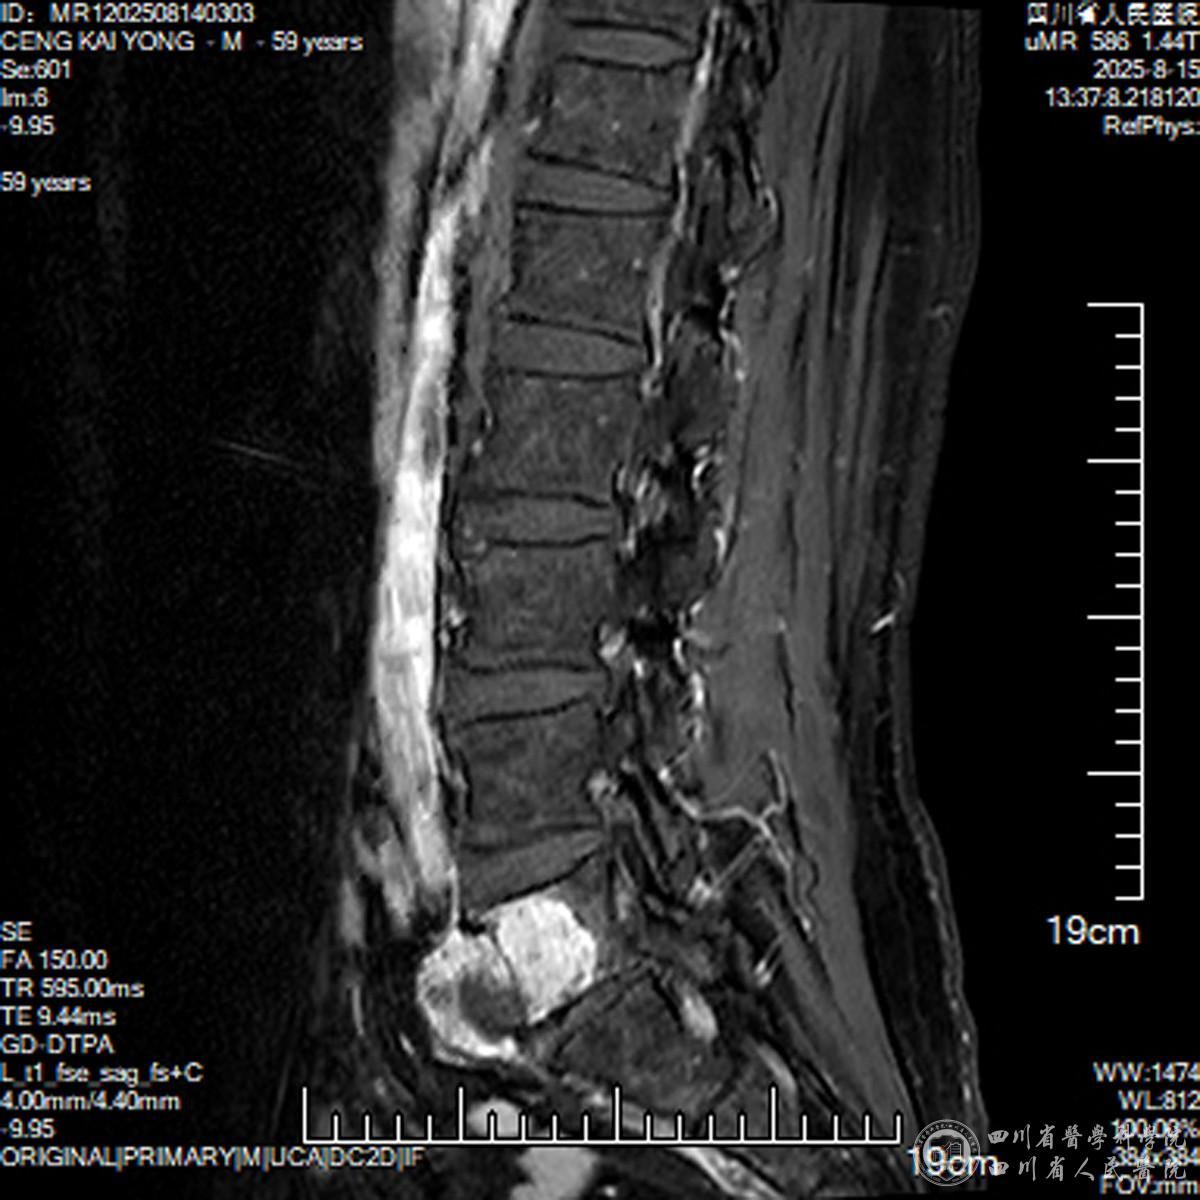

患者8个多月前无诱因出现腰部疼痛,夜间痛明显,让他夜不能寐。辗转多家医院后被确诊为“脊柱肿瘤”,但因肿瘤与椎管内神经、大血管紧密交织,手术风险极高,多家医院束手无策。“不能看着父亲遭罪”,患者子女未放弃,经人推荐找到了我院骨科俞阳主任医师。患者CT、MRI等详尽影像学检查结果显示病情严峻:不仅肿瘤已“吃掉”了部分椎体骨质,更为关键的是肿瘤已突破腰5椎体前方,与前方腹腔大血管紧密粘连;向后压迫椎管内的神经。

腰5椎前方紧贴人体大血管(腹主动脉、下腔静脉),后方保护着支配双腿功能的神经。在此区域手术如同“雷区”排爆,术中任何细微偏差,均可能导致致命性大出血或永久性瘫痪。这一区域被视作脊柱外科的“手术禁区”,手术难度极高、风险极大。面对复杂病情,俞阳团队迅速启动多学科会诊,牵头召集血管外科、麻醉科、肿瘤科、影像科专家联合研判。影像科精准标注肿瘤侵犯范围与解剖关系,血管外科预判血管保护方案,麻醉科制定个性化麻醉计划,肿瘤科评估术后随访策略。经多轮论证,团队确定手术是唯一有效方案——保守治疗只会加重骨质破坏,可能导致瘫痪或危及生命。最终,团队决定采用脊柱外科高难度的“肿瘤整块切除”方案,借助手术机器人实时导航,兼顾肿瘤根治与风险控制。